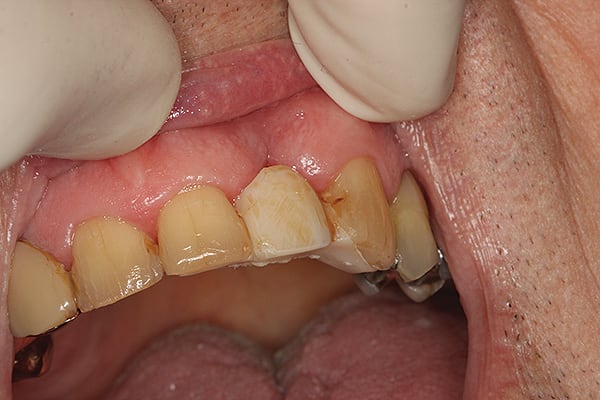

12. Final restoration in place immediately after bonding.